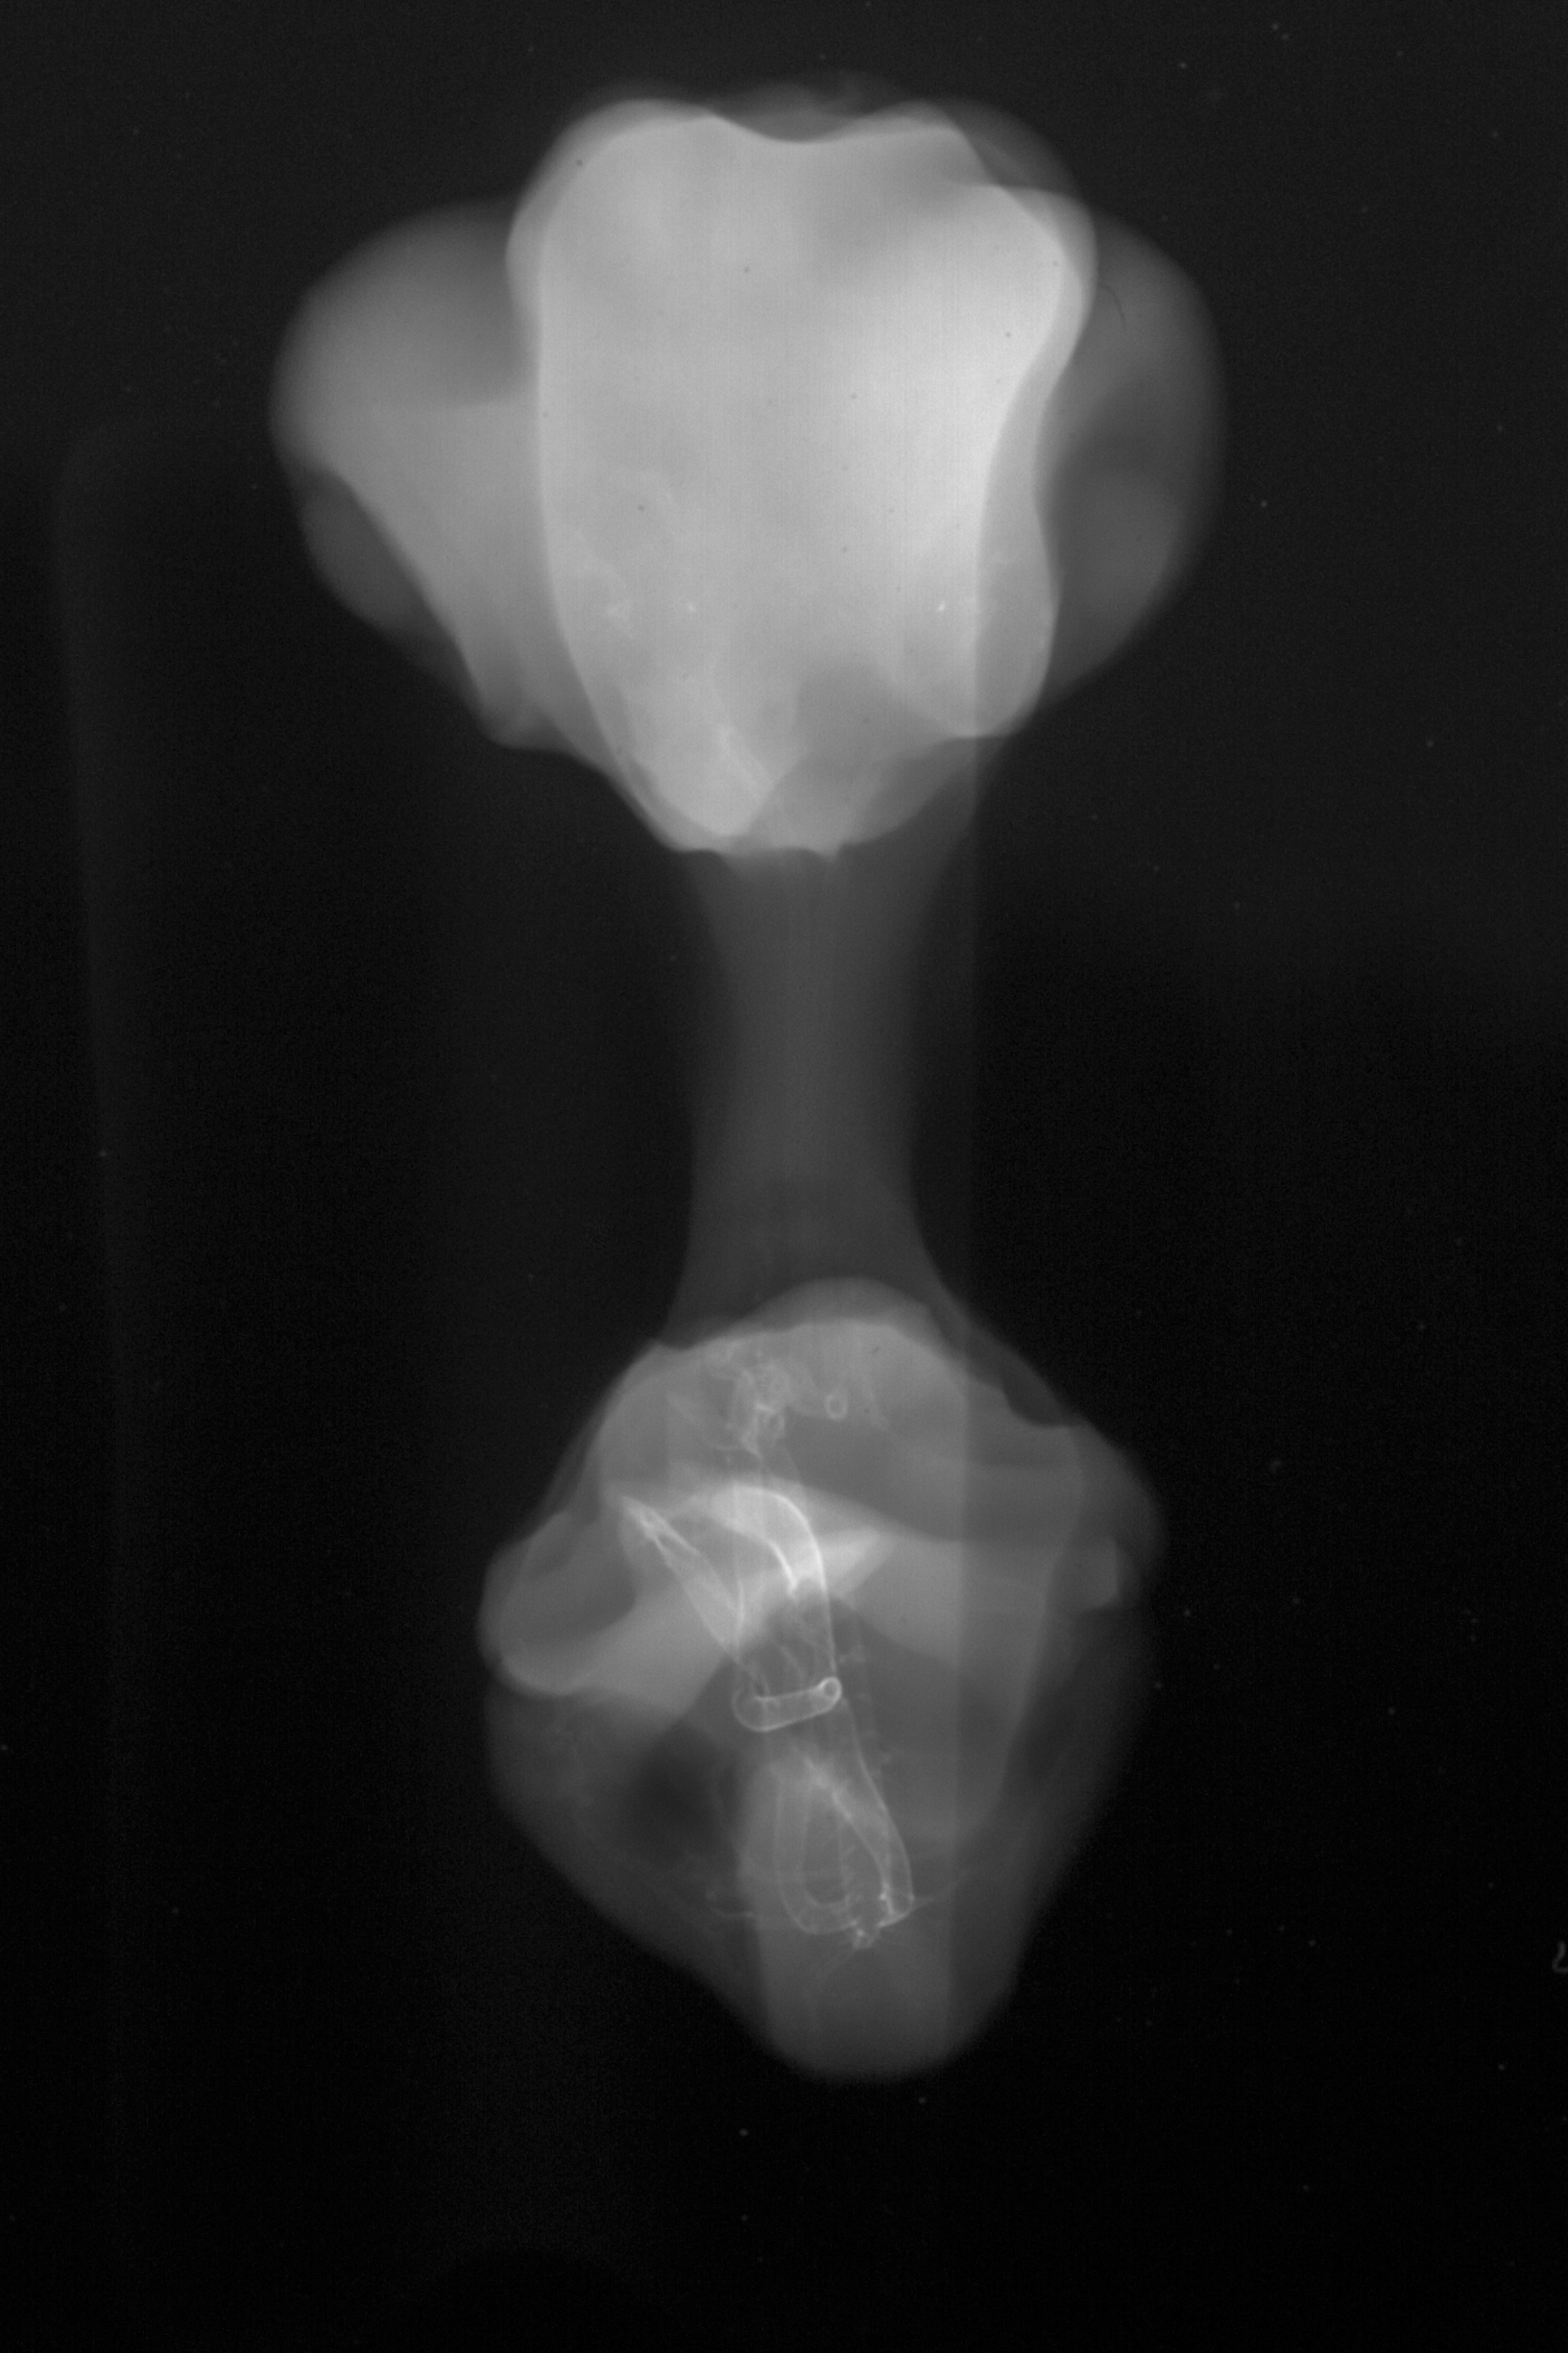

Chick Embryo Microangiography

Hamburger-Hamilton (HH) Stage 31 (approx. 7 days)

X-Ray Micrographs